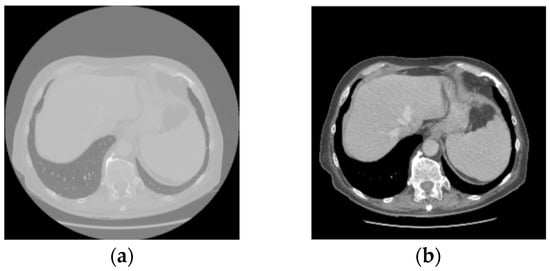

Objectives: Respiratory motion degrades the quantitative accuracy and test–retest (TRT) reliability of fluorine-18 fluorodeoxyglucose ([18F] FDG) positron emission tomography (PET)/computed tomography (CT) in lung cancer. This study investigated whether a deep-learning-based respiratory motion correction (RMC) method improves the TRT reliability and [...] Read more.

Objectives: Respiratory motion degrades the quantitative accuracy and test–retest (TRT) reliability of fluorine-18 fluorodeoxyglucose ([18F] FDG) positron emission tomography (PET)/computed tomography (CT) in lung cancer. This study investigated whether a deep-learning-based respiratory motion correction (RMC) method improves the TRT reliability and image quality of [18F] FDG PET tumor quantification compared with non-motion-corrected (NMC) reconstructions. Methods: Thirty-one patients with primary lung cancer underwent three PET acquisitions: whole body free breathing (Scan1), thoracic free breathing (Scan2), and thoracic controlled breathing (ScanCB). Each dataset was reconstructed with and without RMC. Visual assessments of liver motion artifacts, lesion clarity, and PET-CT co-registration were scored. Lung tumors were segmented to derive standardized uptake value max (SUVmax), SUVmean, metabolic tumor volume (MTV), PET-derived lesion length (PLL), and total lesion glycolysis (TLG). Visual image scores and TRT reliability of tumor quantification were compared using Kruskal–Wallis one-way analysis of variance and intraclass correlation coefficients (ICCs). Results: RMC reconstructions achieved higher visual scores of lesion clarity and PET-CT co-registration across all lung lobes and significantly reduced liver motion artifacts compared with NMC reconstructions. Differences in SUVmax, SUVmean, PLL, MTV, and TLG between Scan2 and ScanCB were significantly smaller with RMC than with NMC. ICCs for SUVmax, SUVmean, MTV, and TLG were higher between scans with RMC than NMC reconstructions, indicating improved TRT reliability. Conclusions: The deep-learning-based RMC method improved the image quality and TRT reproducibility of [18F] FDG PET/CT quantification in lung cancer, supporting its potential for routine adoption in therapy-response assessments. Full article